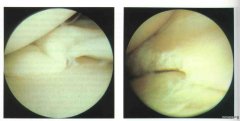

膝关节盘状半月板损伤 由于盘状半月板形态异常,不符合人体运动的生理功能要求,故较正常的半月板更容易退变和损伤,且损伤通常发生较早,不少病人无明显外伤史。 膝关节盘状...